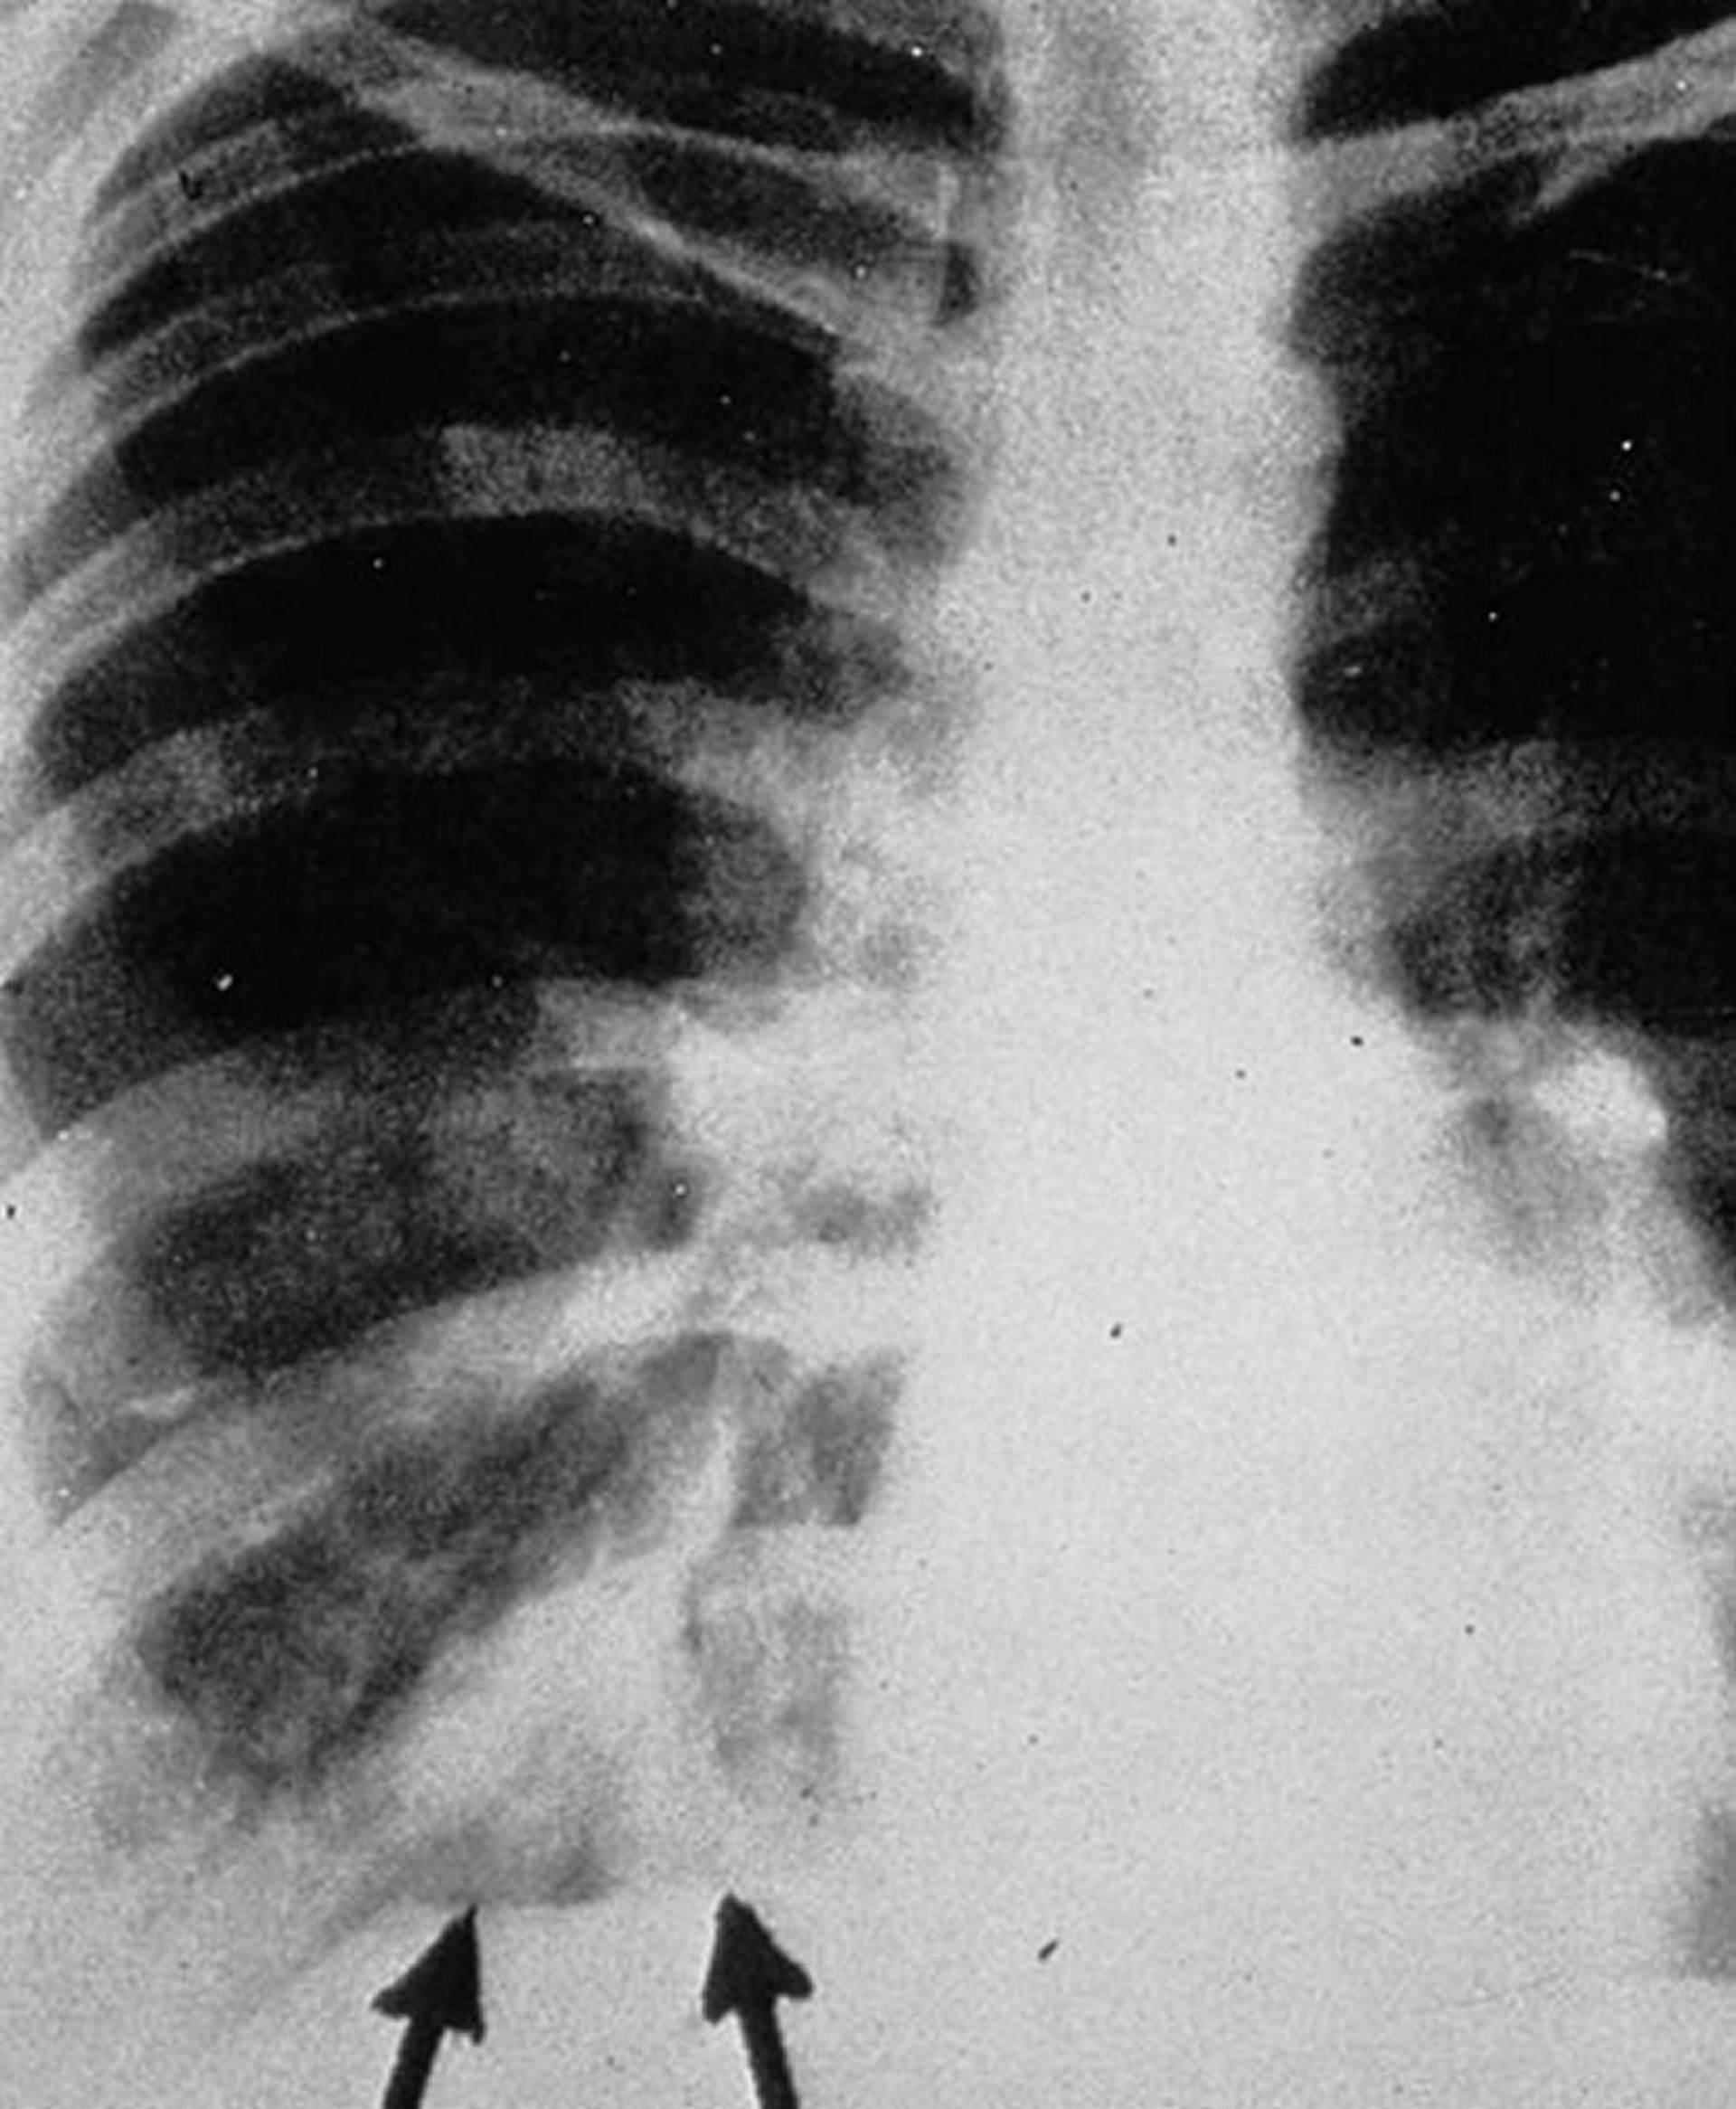

Posteroanterior chest x-ray shows "gloved finger" shadows (arrows), appearing as branched tubular densities that represent intrabronchial exudates with bronchial wall thickening.

By permission of the publisher. From Groll A, Walsh T. In Atlas of Infectious Diseases: Fungal Infections. Edited by GL Mandell and RD Diamond. Philadelphia, Current Medicine, 2000.